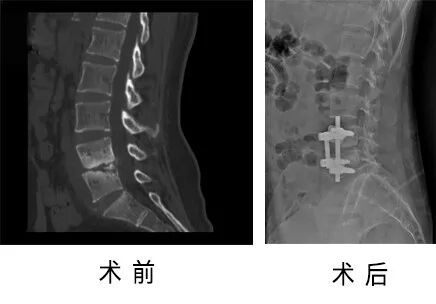

50歲的李阿姨,3年前出現(xiàn)腰背部酸痛不適,臥床休息后緩解,站立活動后加重,癥狀時輕時重,并沒有進行系統(tǒng)治療。

近1周以來,腰背部酸痛癥狀加重,并出現(xiàn)雙下肢麻木,難以忍受,就診于省級知名骨科專家、邦爾骨科集團首席專家、嘉興邦爾骨科醫(yī)院院長趙凱教授的專家門診,診斷為“退行性腰4椎體滑脫、腰椎管狹窄癥”。

趙凱教授帶領(lǐng)脊柱外科團隊為其進行了“后路L4椎體滑脫切開復(fù)位內(nèi)固定+L4全椎板切除椎管擴大減壓+L4/5椎間盤切除+Cage植入融合術(shù)”,術(shù)后患者疼痛癥狀明顯改善。

術(shù)前術(shù)后對比圖